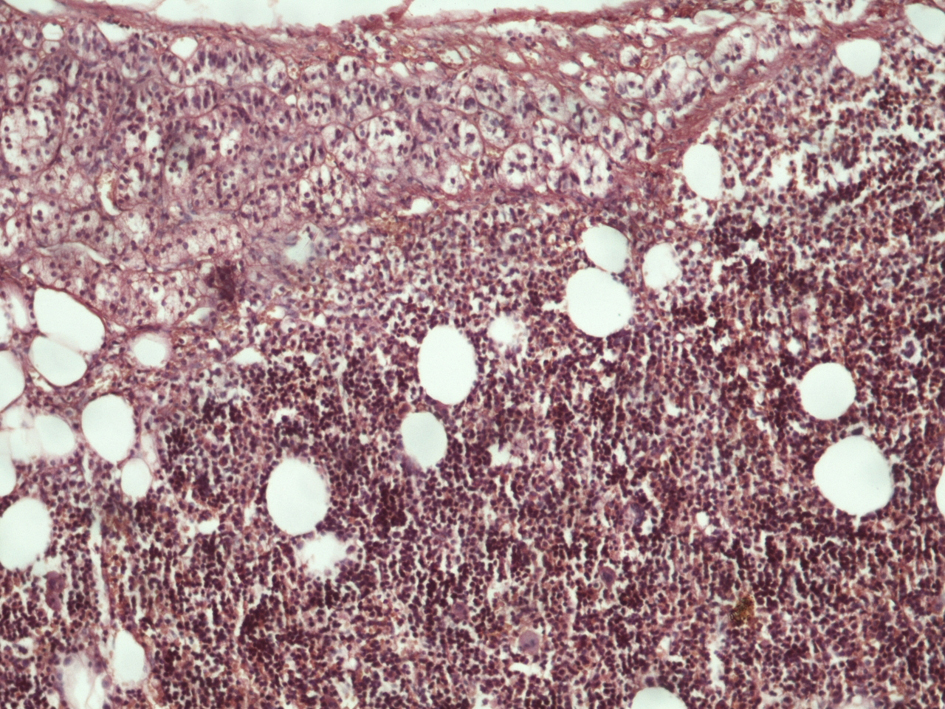

Myelolipomas are well circumscribed in gross inspection, but are rarely encapsulated. Their color varies from pale yellow to deep red or brown depending upon the relative proportion of fat and hematopoietic elements. The contour of the adrenal myelolipoma is smooth, wavy, or irregular and may shoe intermingling of cortical cells with elements of the myelolipoma. The surrounding cortical cells can be relatively normal in appearance or compressed (Fig. 1). There is a variable mixture of mature fat with hematopoietic elements, often with full representation of the major cell lines (Fig. 2). Rarely foci of ossification are seen.

![]() Click for large image | Figure 1. Histological section of adrenal gland showing both normal adrenal tissue and myelolipoma (hematoxylin-eosin × 120). |